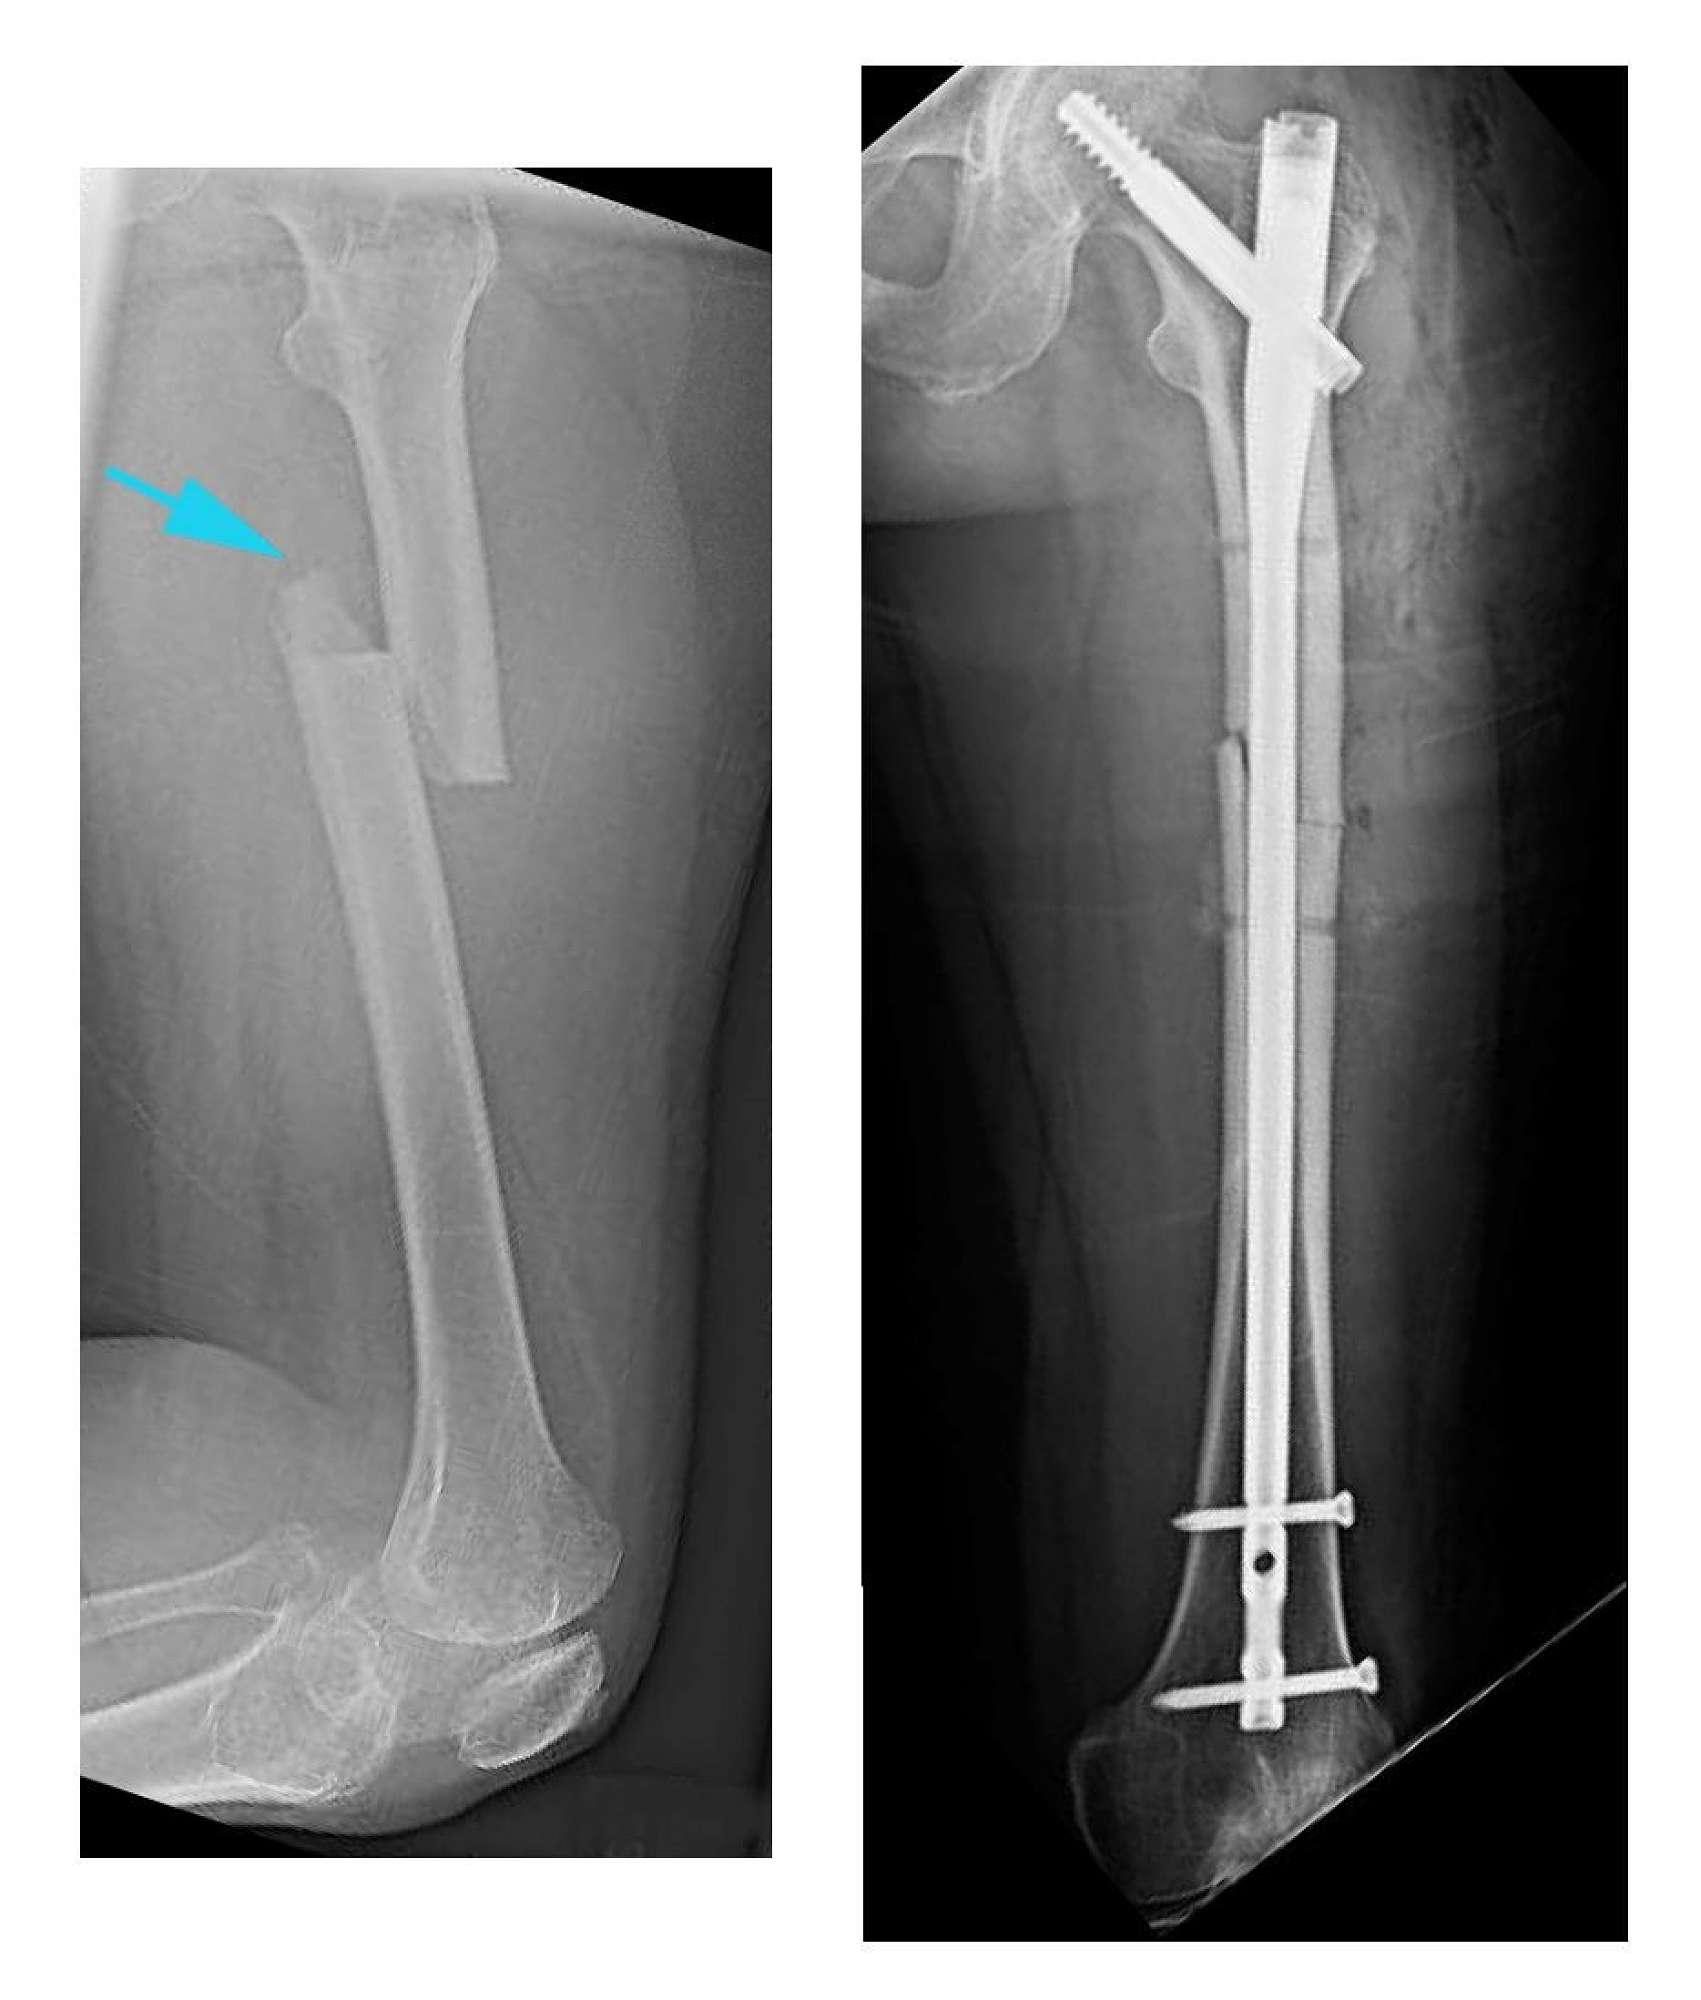

These X-rays show a broken thigh bone on the left, with modern day intra medullary rod fixation of the fracture on the right.

The outdated technique of traction for six weeks to treat such fractures, which has till recently been used in Tonga, will now be supplanted by more modern-day fixation techniques.